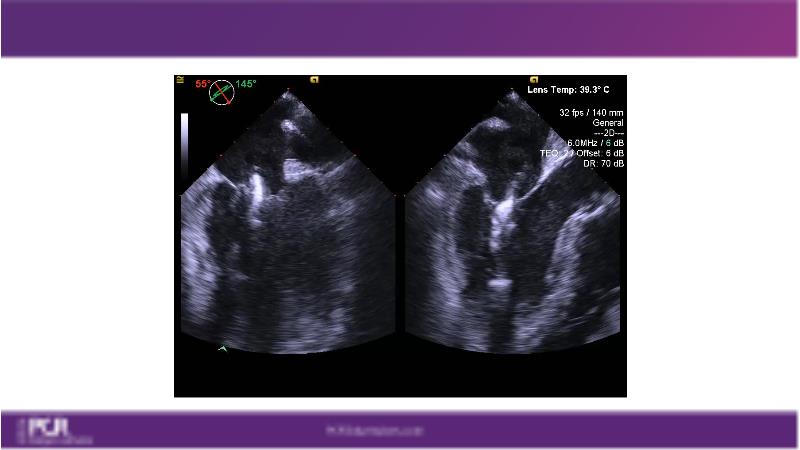

Watch this session to get an overview of a new TEER device, follow the step-by-step procedure related to initial experiences with this device for a Japanese patient with degenerative mitral regurgitation, learn about the latest data from RCT and registries, and follow discussions of challenging TEER cases!

- To learn procedural step-by-step of novel device